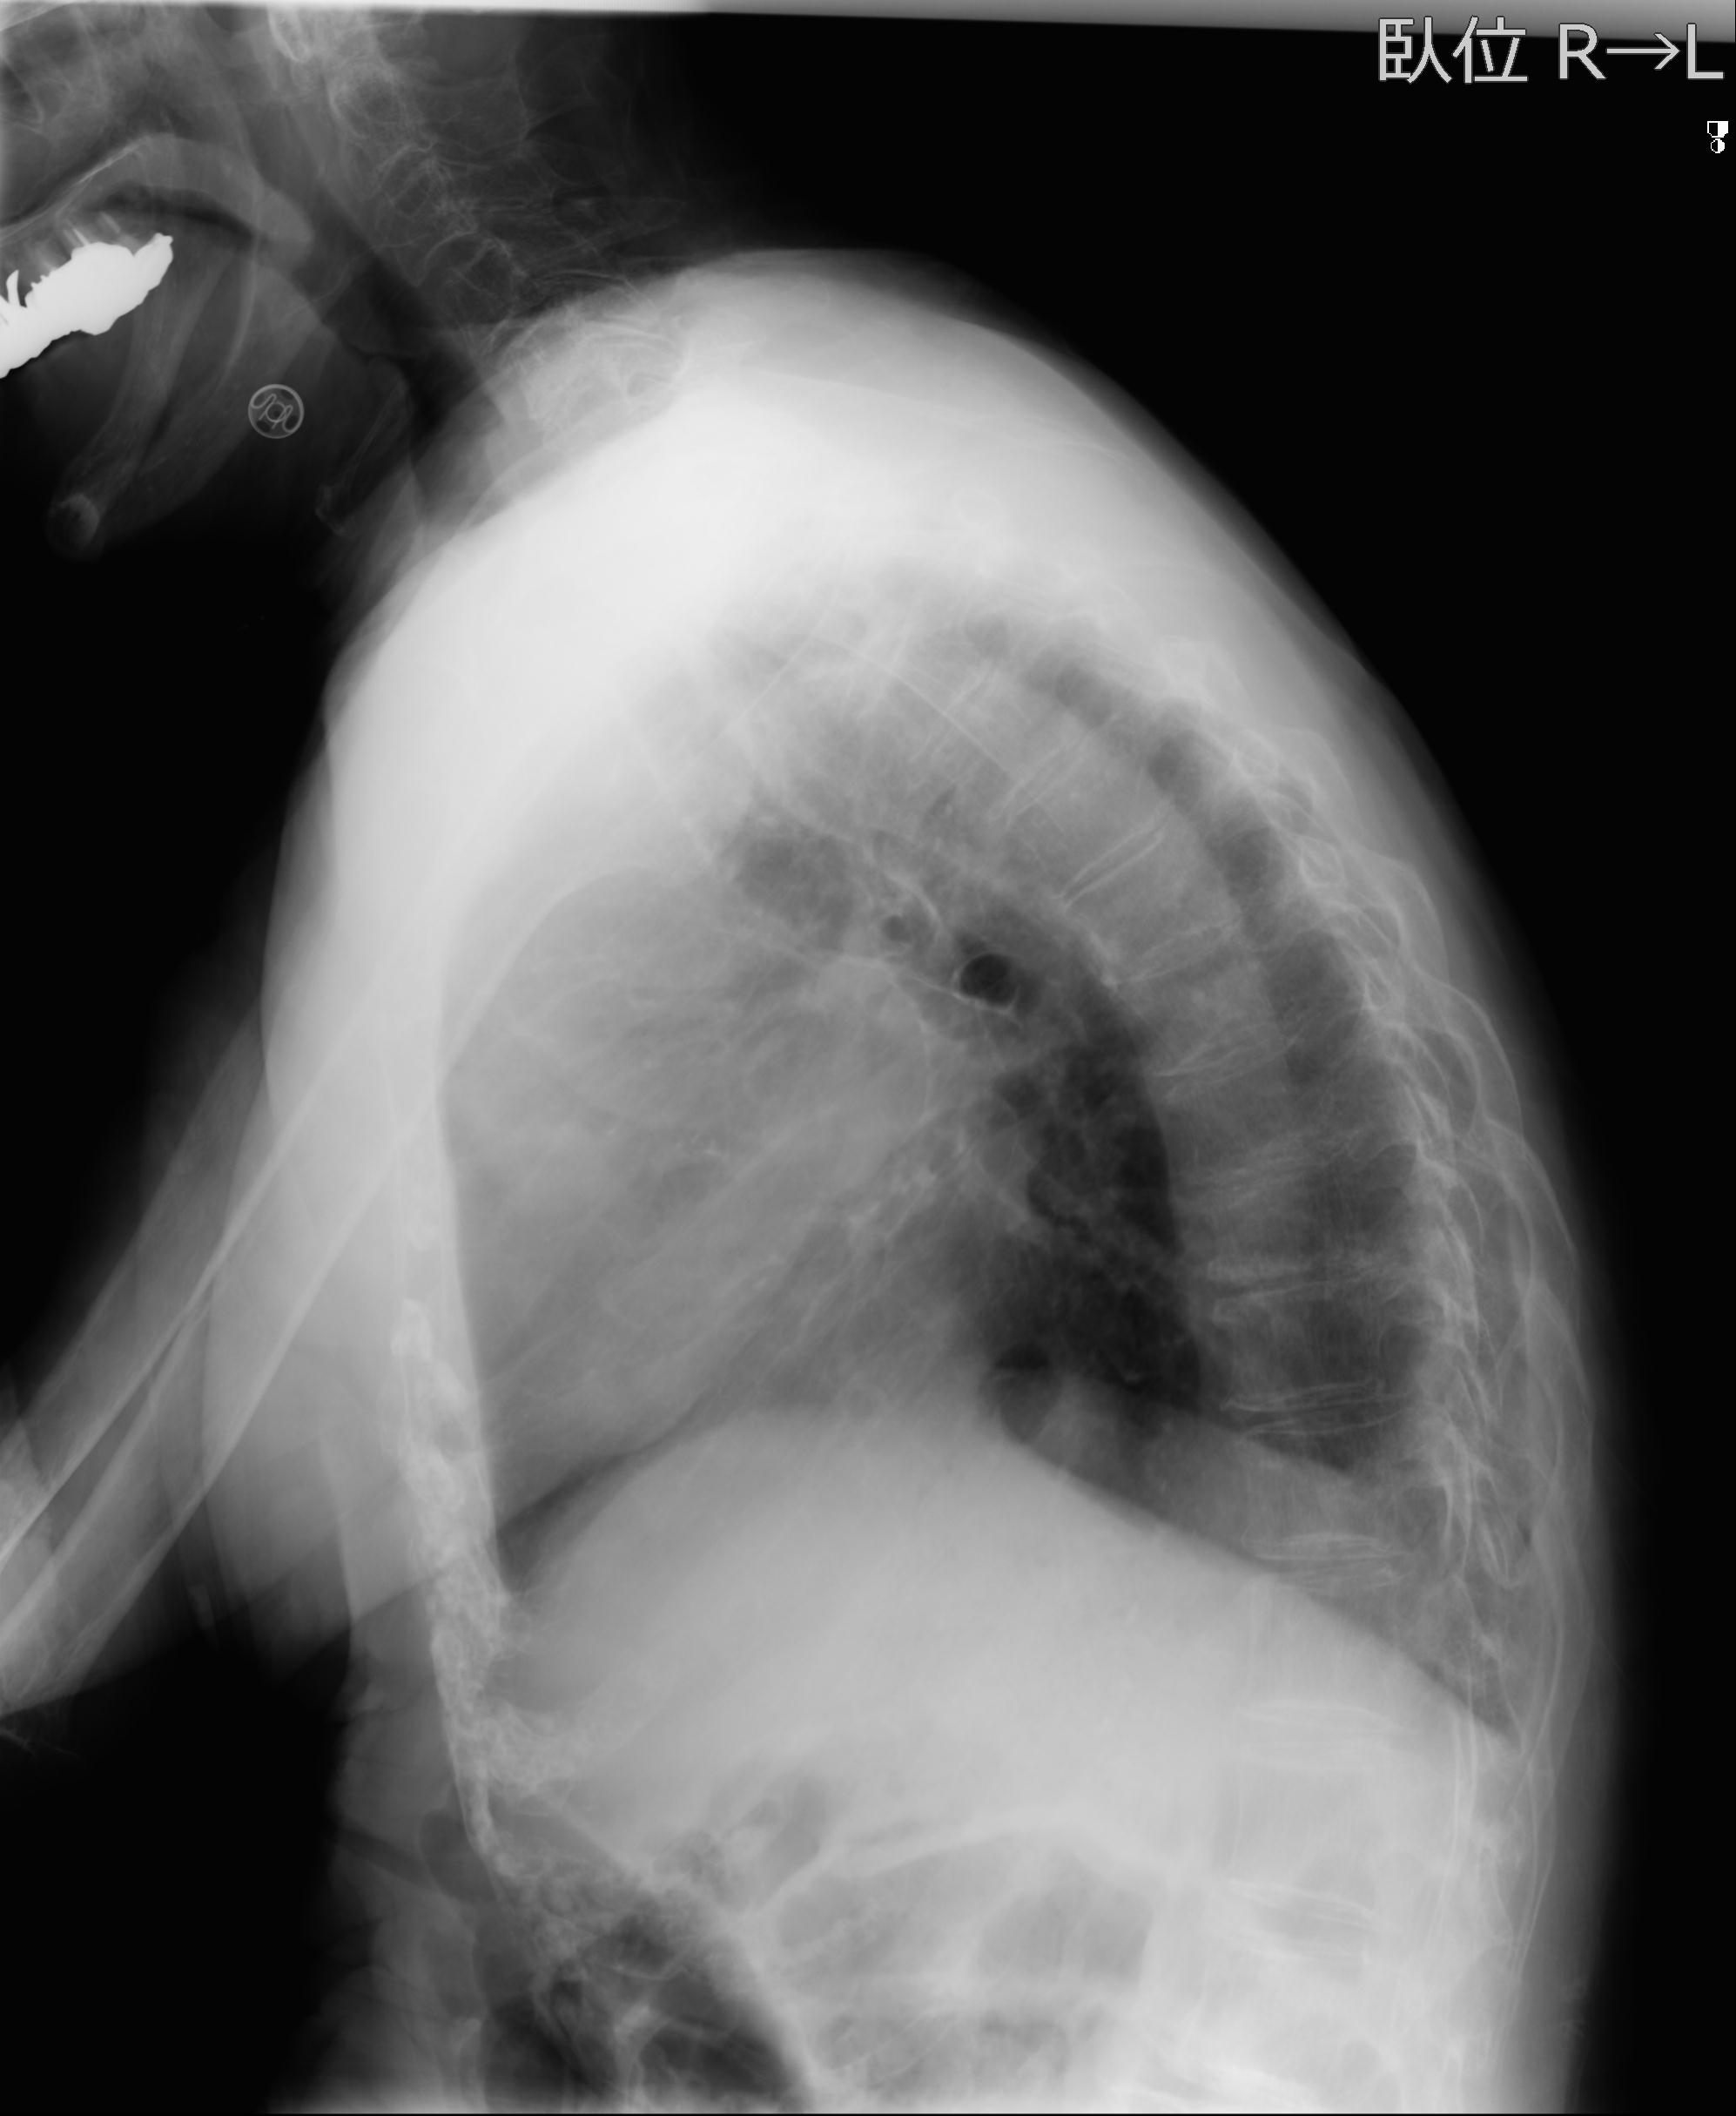

91983 11/16 左膝 2R 11/18 2R 55歳男性 脛骨骨切り術